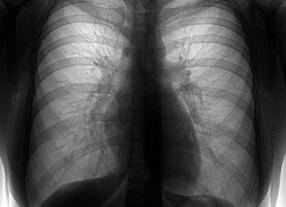

Каждому человеку необходимо ежегодно проходить профилактическое обследование. Это позволяет медицинским специалистам обнаружить ранние стадии таких опасных патологий, как туберкулез и опухолевидные образования. Изучение состояния здоровья пациента проводится по итоговым данным лабораторных исследований и флюорографии – интерпретация ее результатов дает возможность врачу оценить состояние легких.

Флюорографическое исследование лёгких и сердца выполняется для диагностики туберкулёза, а также с целью определения других патологий органов дыхания. Результаты флюорографии помогают оценить состояние бронхов, лёгких. Увидеть воспалительные процессы, спайки, отклонения со стороны диафрагмы. Окончательный диагноз ставит врач-рентгенолог после изучения снимка.

В основу метода флюорографии положена способность рентгеновских лучей проникать через плотную поверхность легочной ткани и проявляться на специальной пленке в виде рисунка легких, полученного посредством флюоресцирующих частиц.

Сам снимок, полученный после обследования, выглядит неоднородно. Связанно это с тем, что органы, расположенные в области грудной клетки, имеют свойство по-разному поглощать поступающее излучение.

На снимке можно увидеть сердце и бронхи в виде светлых пятен. Легочная ткань здорового человека будет отображена равномерно, без неоднородных вкраплений.

Если на легких имеются какие-либо патологии, то снимок покажет либо затемненные области, когда корни легких и сама ткань уплотнены, либо проявятся светлые участки, свидетельствующие о том, что ткань имеет высокую воздушность.